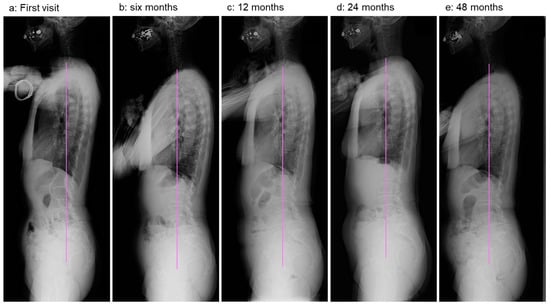

2.4. Image Examinations after Six Months of Daily Physical Exercise